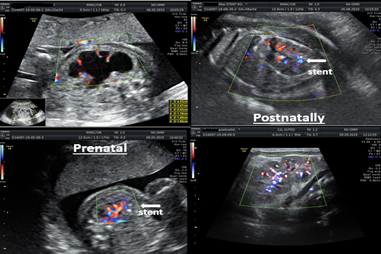

Figure 7 shows a case of nephroamniotic shunting for unilateral hydronephrosis of grade III to IV in a fetus at 22 weeks of gestation. The "SDE-MED" stent remained in the left kidney of the fetus for 17 weeks, and 6 days, delivery was performed through the natural birth canal, the stent was removed after the birth of the child in the maternity ward, and postnatal correction of the urinary system defect was not required.

Figure 7 Unilateral nephroamniotic shunting at 22 weeks of pregnancy for hydronephrosis of grade III to IV on the right.